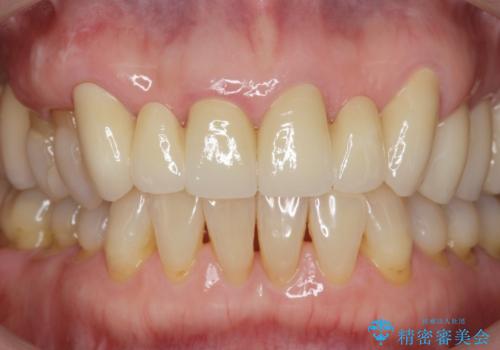

不自然な前歯ブリッジ ジルコニアブリッジによるやり替え

- 20年前に入れたブリッジの見た目の改善を求めて来院されました。

丁寧に現在装着されているブリッジを除去後、精度の高いジルコニアブリッジで審美性の改善を計画します。

- 66万円(仮歯・ジルコニアクラウン×6)費用は治療当時の料金となります

前歯に限らず拡大鏡を用いた精密な形成・シリコンを用いた精度の高い印象を徹底することで治療全体の質を高め、審美性だけでなく長期的な予後を期待することができます。